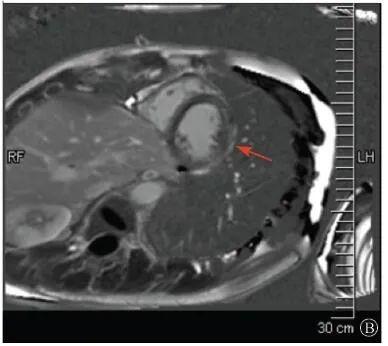

案例介紹:患者男性,20歲,因為"胸痛4個月,加重1月余"于2019年7月10日入院。患者2019年4月無明顯誘因出現(xiàn)心前區(qū)隱痛,VAS 3分,無放射,無胸悶、憋氣、活動后氣短,每月發(fā)作1~2次,未在意。同年5月體檢發(fā)現(xiàn),肌酸激酶(CK)2928 U/L、肌酸激酶MB質(zhì)量(CK-MB)46 U/L、心肌肌鈣蛋白I(cTnI)0.055 ng/ml。6月初,患者"感冒"后出現(xiàn)心前區(qū)疼痛加重,為過電樣疼痛,VAS 5分,無放射,持續(xù)約30~60 min可好轉(zhuǎn),胸痛每周約發(fā)作2次,否認呼吸困難、胸悶、心悸,否認活動耐量下降。6月8日,患者就診于外院查血生化:CK 1 215→1433 U/L,CK-MB 47 U/L,cTnI 30.17→31.79 ng/L;血脂(-);抗核抗體譜(-);超聲心動圖:左室增大,左室舒張末內(nèi)徑57 mm,左室射血分數(shù)39%,輕度二尖瓣關閉不全;磁共振心肌灌注延遲動態(tài)成像(圖1):左室稍增大,收縮功能稍減低;基底部至心尖部左室下壁及側(cè)壁、心尖部左室前壁心外膜下心肌纖維化,考慮非缺血性心肌?。患‰妶D:肌源性損害(偏慢性)。診斷"多發(fā)性肌炎、心肌損傷",予患者倍他樂克緩釋片23.75 mg/d、培哚普利0.5 mg/d、螺內(nèi)酯20 mg/d口服,患者未再出現(xiàn)心前區(qū)疼痛,但步行1 km左右會出現(xiàn)氣短、乏力。為進一步明確心力衰竭病因收入我院?;颊呱细咧衅鸪霈F(xiàn)體育課等劇烈活動后雙下肢明顯乏力,不能耐受1 km長跑類運動,日常體力活動不受影響,否認肌肉酸痛等不適。此次發(fā)病以來,一般情況尚可,否認尿量減少,體重無明顯變化。既往史:否認高血壓、冠心病、糖尿病病史。個人史:否認特殊毒物藥物接觸史,無煙酒嗜好?;橛贰⒓易迨罚何椿槲从?,否認家族類似病史,否認遺傳病史。入院查體:脈搏69次/min,血壓112/70 mmHg,指氧(自然狀態(tài))98%,體質(zhì)指數(shù)21.1 kg/m2;無皮疹;雙肺呼吸音清;心律齊,未聞及雜音;肝脾不大;雙側(cè)腓腸肌肥大,肌肉無壓痛;四肢肌力Ⅴ級、肌張力正常。雙下肢不腫。輔助檢查:入室床旁超聲心動圖提示左室壁運動普遍減低,心尖部、左室下后壁為著,肌小梁增多。

左室壁較廣泛心外膜下延遲強化,可見左室下后壁肌小梁增多(箭頭所示)

圖1 患者外院磁共振心肌灌注延遲動態(tài)成像